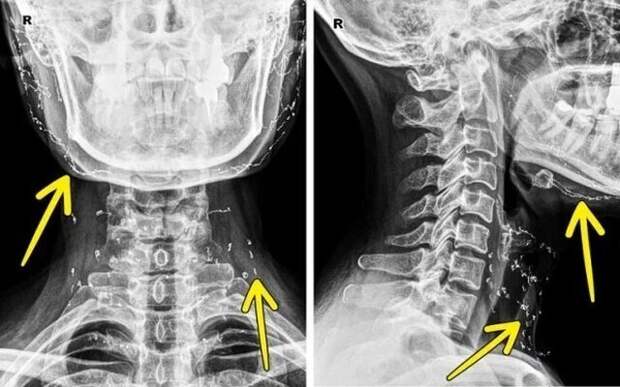

Рентген пациента, который весит 185 килограмм  Рентген пациента, который прошел процедуру подтяжки лица золотыми нитями